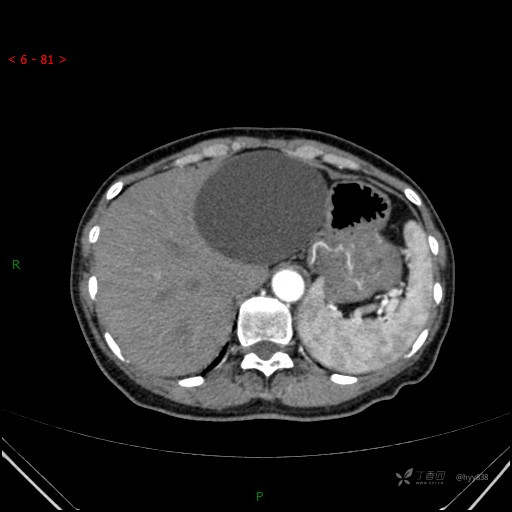

增强动脉期